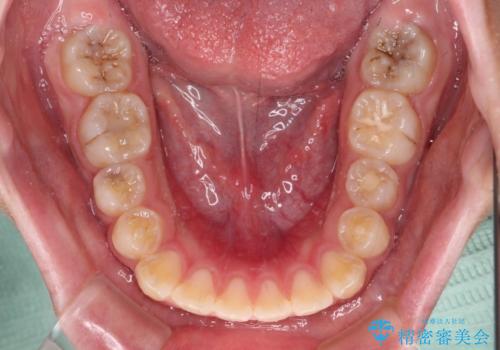

- 前歯が開いて飛び出していることを気にして来院された患者様です。

舌の突出癖により上下前歯は接触できず、更には前方に押し出されて出っ歯になっている状態でした。

上下左右の第一小臼歯4本を抜歯し、ワイヤー装置での抜歯矯正を行っていくのですが、原因である舌の突出癖を改善しないことには治療がうまく進められないため、舌のトレーニングを徹底するよう指導していくこととしました。